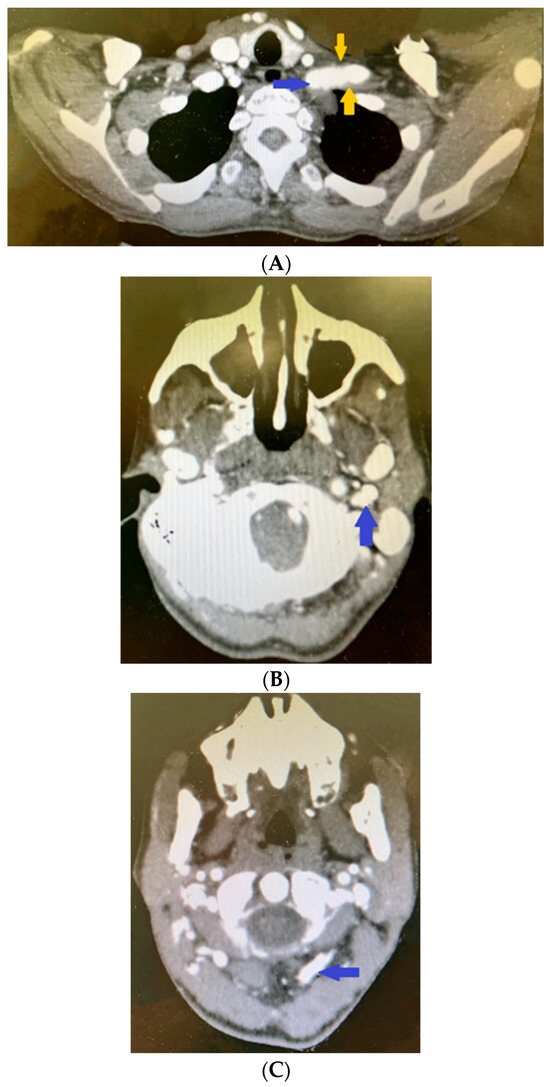

The patient saw her general practitioner in October 2021 due to swelling in the neck region and a pulsing lump on the left side of the neck. Following a clinical assessment, the physician recommended an ultrasound, which showed dilatations of 10 mm in the right external carotid artery and 12 mm in the left external carotid artery (with aneurysm) (normal range for women: 5.1 ± 1.0 mm). For these findings, contrast-enhanced brain computed tomography (CT) and angiography were performed. The results revealed the following for the extracranial vessels on the right. A dilation of 11.5 cm was seen in the right subclavian artery (normal 0.7–1.0 cm) (Figure 5A), with a subsequent segment of 30 mm with parietal thrombosis (Figure 5B) with occlusions and significant stenosis (Figure 5A).

Figure 5.

Contrast-enhanced computed tomography revealing (A) dilated right subclavian artery (blue arrow) followed by significant stenosis (red arrows); (B) parietal thrombosis in the right subclavian artery (yellow arrow); (C) aneurismal dilatation of the right external carotid artery (blue arrow); (D) fusiform dilatation of the right vertebral artery (blue arrow).

The common carotid artery had calcium plaques in the area of bifurcation without significant stenosis. The internal carotid artery was seen with a calcium plaque in the ostium without significant stenosis but with diffuse calcium plaques in the cavernous and petrous segments and significant stenosis in the petrous segment. The external carotid artery presented postostiumally with an 8.5 to 7.5 mm aneurysmal dilatation (Figure 5C).

In addition, calcium plaques and pathological fusiform dilatations were found in the vertebral artery (Figure 5D).

Significant pathological deviations were also present in the left extracranial vessels; the left subclavian artery had parietal thrombosis and a fusiform aneurysmal dilatation of 68 mm after the ostium, with maximum axial dimensions of 50 by 31 mm (Figure 6A).

Figure 6.

Contrast-enhanced computed tomography revealing (A) dilated left subclavian artery (blue arrow) and parietal thrombosis in the left subclavian artery (yellow arrows). Contrast-enhanced computed tomography revealing (B) aneurismal dilatation of left internal carotid artery. Contrast-enhanced computed tomography revealing (C) fusiform dilatation of left vertebral artery.

The CT scan revealed calcium plaques in the bifurcation region of the common carotid artery, but no discernible stenosis. Calcium plaques also impacted the internal carotid artery, which resulted in stenosis at the pars petrosa–pars cavernosa transition and intracranial aneurysmal dilation (Figure 6B).

Immediately after the ostium, an 11.5 to 12.5 mm aneurysmal dilatation was seen in the external carotid artery. Pathological fusiform dilatation was also seen in the vertebral artery (Figure 6C).